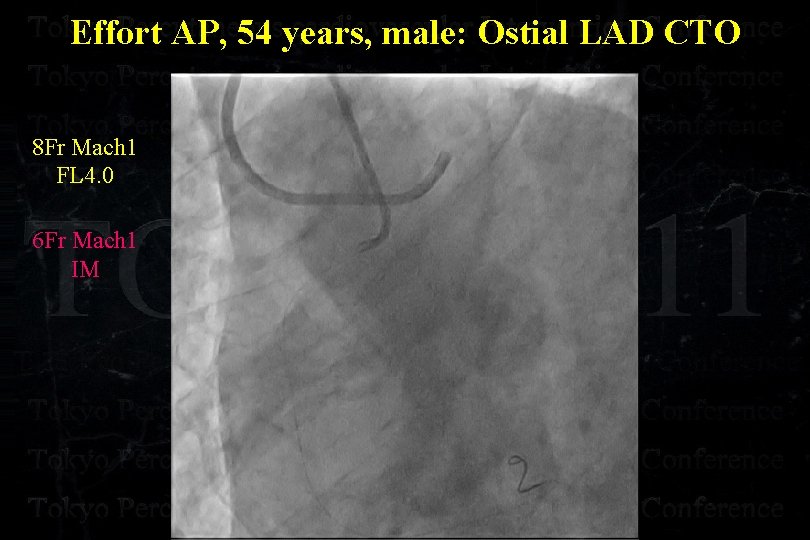

Effort AP, 54 years, male: Ostial LAD CTO

Effort AP, 54 years, male: Ostial LAD CTO

Effort AP, 54 years, male: Ostial LAD CTO

Effort AP, 54 years, male: Ostial LAD CTO

Effort AP, 54 years, male: Ostial LAD CTO

Effort AP, 54 years, male: Ostial LAD CTO

Effort AP, 54 years, male: Ostial LAD CTO Separated Conus Branch !

Effort AP, 54 years, male: Ostial LAD CTO 8 Fr Mach 1 FL 4. 0 6 Fr Mach 1 IM